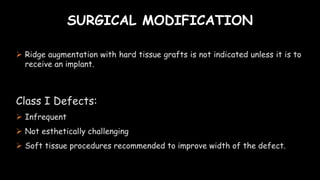

The document discusses pontic design for fixed dental prostheses. It covers pretreatment assessment of residual ridge contours, classifications of ridge deformities, surgical modification techniques, and ideal requirements for pontics. Pontic designs are classified based on their shape and materials. Factors in pontic selection include esthetics and oral hygiene. Common designs for anterior and posterior regions are described, including sanitary, ovate, and saddle pontics. Biological considerations for pontic design involve maintaining the residual ridge, abutment teeth, and supporting tissues.